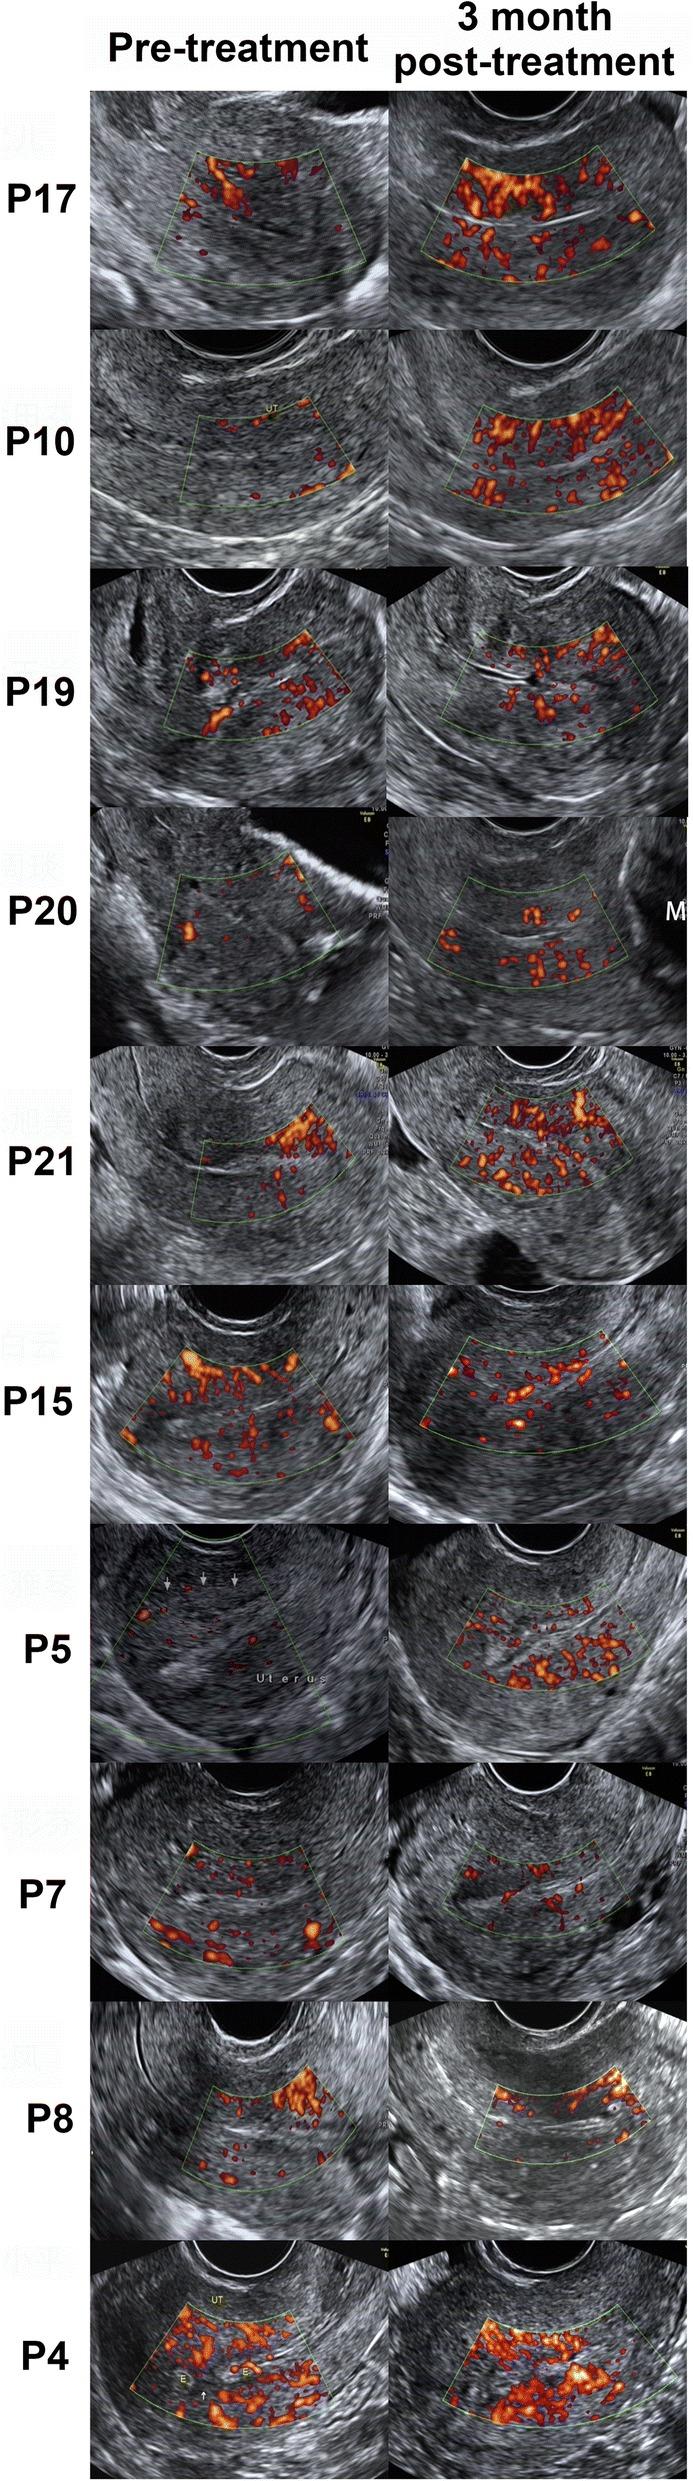

Twenty-six patients who suffered from infertility caused by recurrent IUA were enrolled in this prospective, non-controlled, phase I clinical trial with a 30-month follow-up. During the procedure, 1 × 10 umbilical cord-derived mesenchymal stromal cells (UC-MSCs), loaded onto a collagen scaffold, were transplanted into the uterine cavity following an adhesion separation procedure. Medical history, physical examination, endometrial thickness, intrauterine adhesion score and the biological molecules related to endometrial proliferation and differentiation were assessed both before and 3 months after cell therapy.

No treatment-related serious adverse events were found. Three months after the operation, the average maximum endometrial thickness in patients increased, and the intrauterine adhesion score decreased compared to those before the treatment. A histological study showed the upregulation of ERα (estrogen receptor α), vimentin, Ki67 and vWF (von Willebrand factor) expression levels and the downregulation of ΔNP63 expression level, which indicates an improvement in endometrial proliferation, differentiation and neovascularization following treatment. DNA short tandem repeat (STR) analysis showed that the regenerated endometrium contained patient DNA only. By the end of the 30-month follow-up period, ten of the 26 patients had become pregnant, and eight of them had delivered live babies with no obvious birth defects and without placental complications, one patient in the third trimester of pregnancy, and one had a spontaneous abortion at 7 weeks.